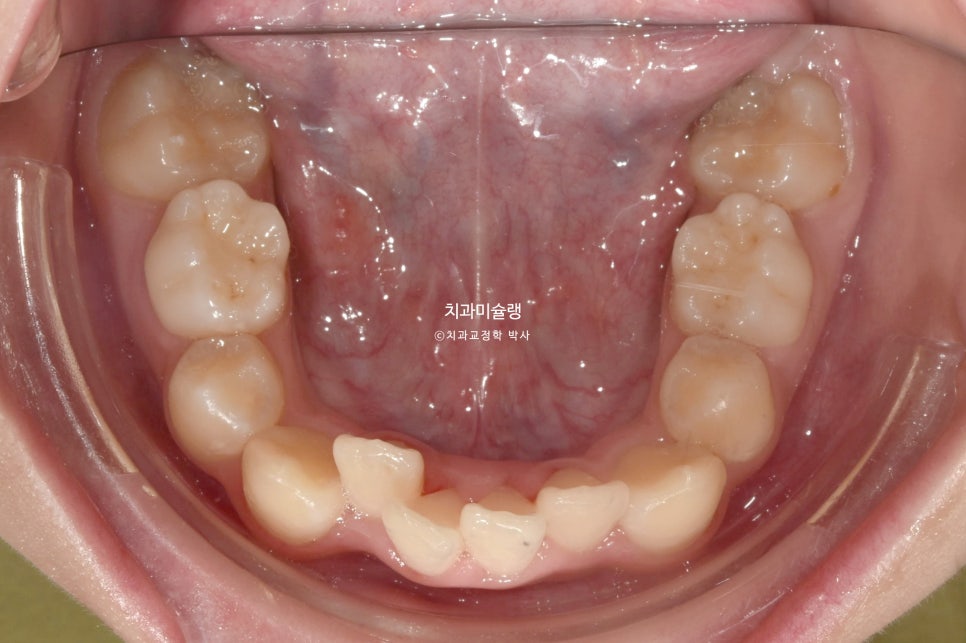

아랫니도 삐뚤삐뚤 합니다.

배열은 좋습니다. 일년사이 마지막 남아있던 유치가 빠지고 영구치가 올라왔습니다.

아쉬운점은 새로 나온 아래 두번째 작은어금니가 약간 회전된 상태로 나왔다는 점이죠.

한국에 있었다면 파워체인 고무줄을 걸어 작은어금니를 제자리로 돌려줬겠지만 해외에서 중간체크 없이 인비절라인만으로는 하악소구치 회전까지 도모하긴 어려워 그대로 두기로 합니다.